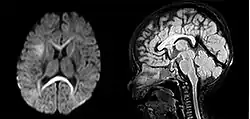

Macrocephaly from hydrocephalus

Macrocephaly from megalencephaly